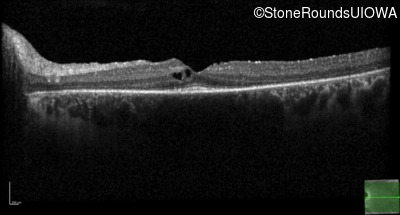

Optical Coherence Tomography - Right -

20/20 -1

Exemplar / OCT Stack

Optical Coherence Tomography - Left -

20/20